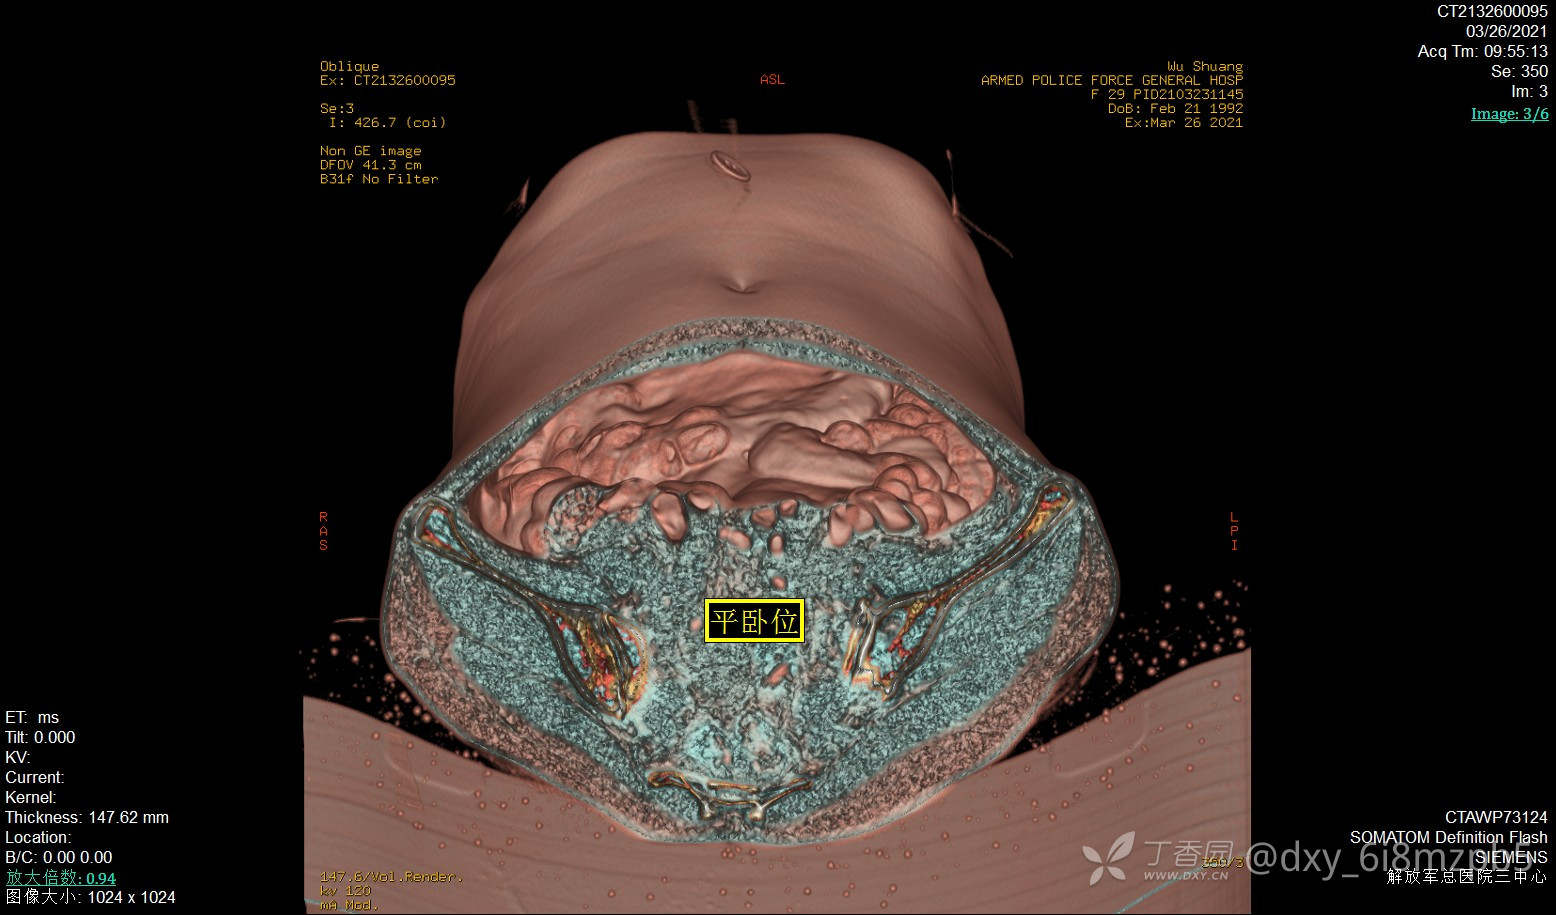

2021-3-26平卧位,左下腹18#套管针穿刺,腹腔注气2000ml,人工气腹后腹部多体位平扫,GE图像工作站进行数据VR成像(腹膜腔三维成像):

平卧位:腹膜腔气腹空间完整,肝脾形态位置正常,结肠小肠肠管平面分布,管径大致形态正常。结肠内容物偏多,48小时口服显影线位于横结肠左半以远。子宫形态大小正常。

平卧位图:中下腹肠管平铺,未见腹壁粘连。